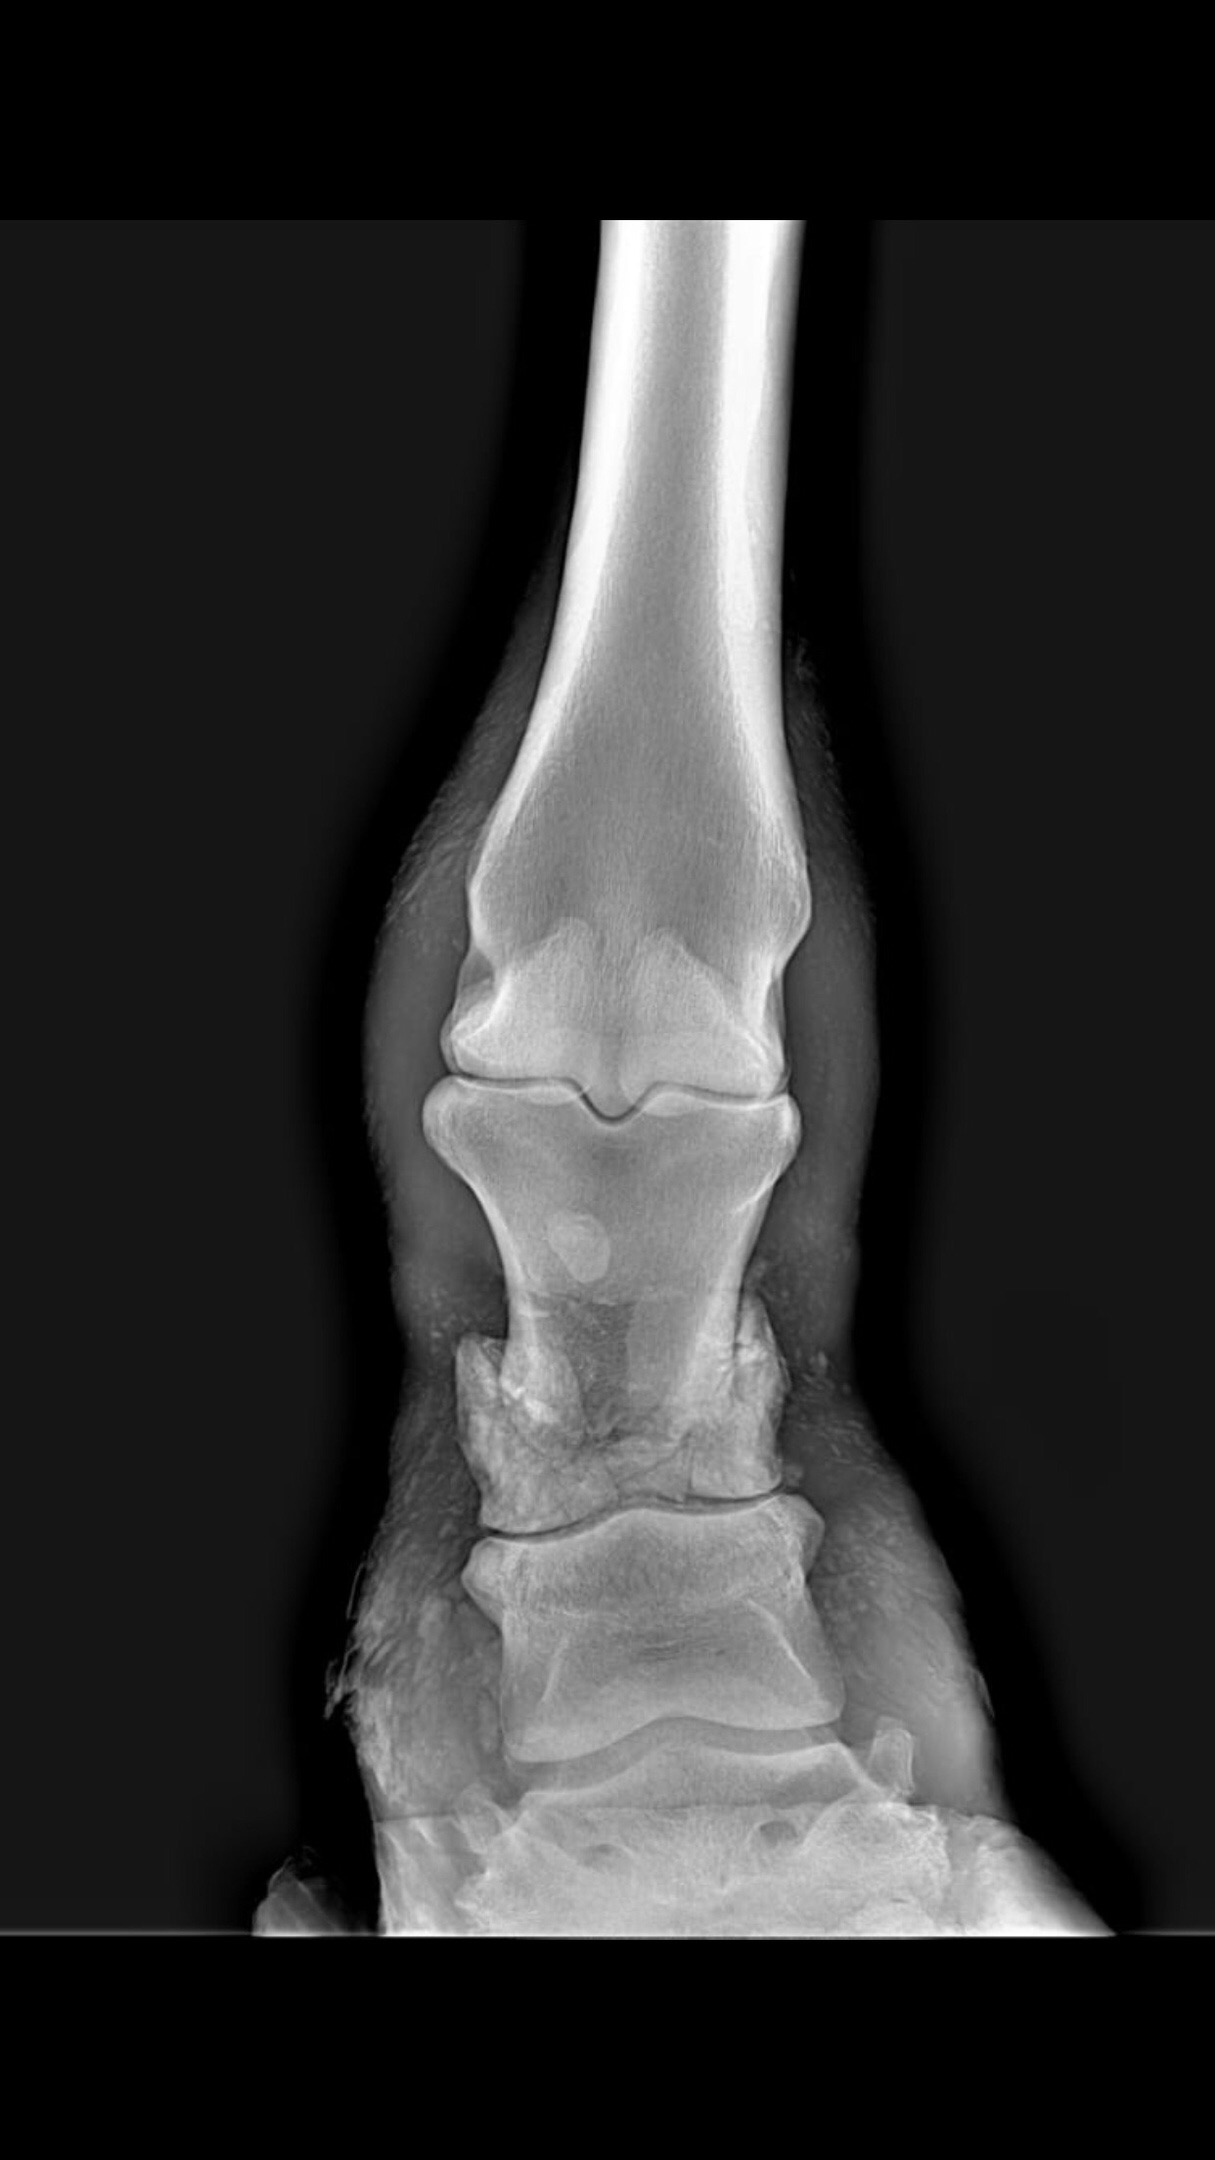

Но там перелом такой...

upload_2020-4-25_22-17-45.jpeg

Вот как ему срастаться?

Перелом компрессионный,вопрос срослось бы блин

Вколоченный оскольчатый перелом :eek: Ну тогда она должна была как то вдавить так кость...интересно..

А у нее кровь давно брали?просто уж очень странный перелом.У нее с кальцием все нормально?Страшно чтоб у нне хруркость кости не повысилась а то одно будет лечиться второе не дай бог колечиться.